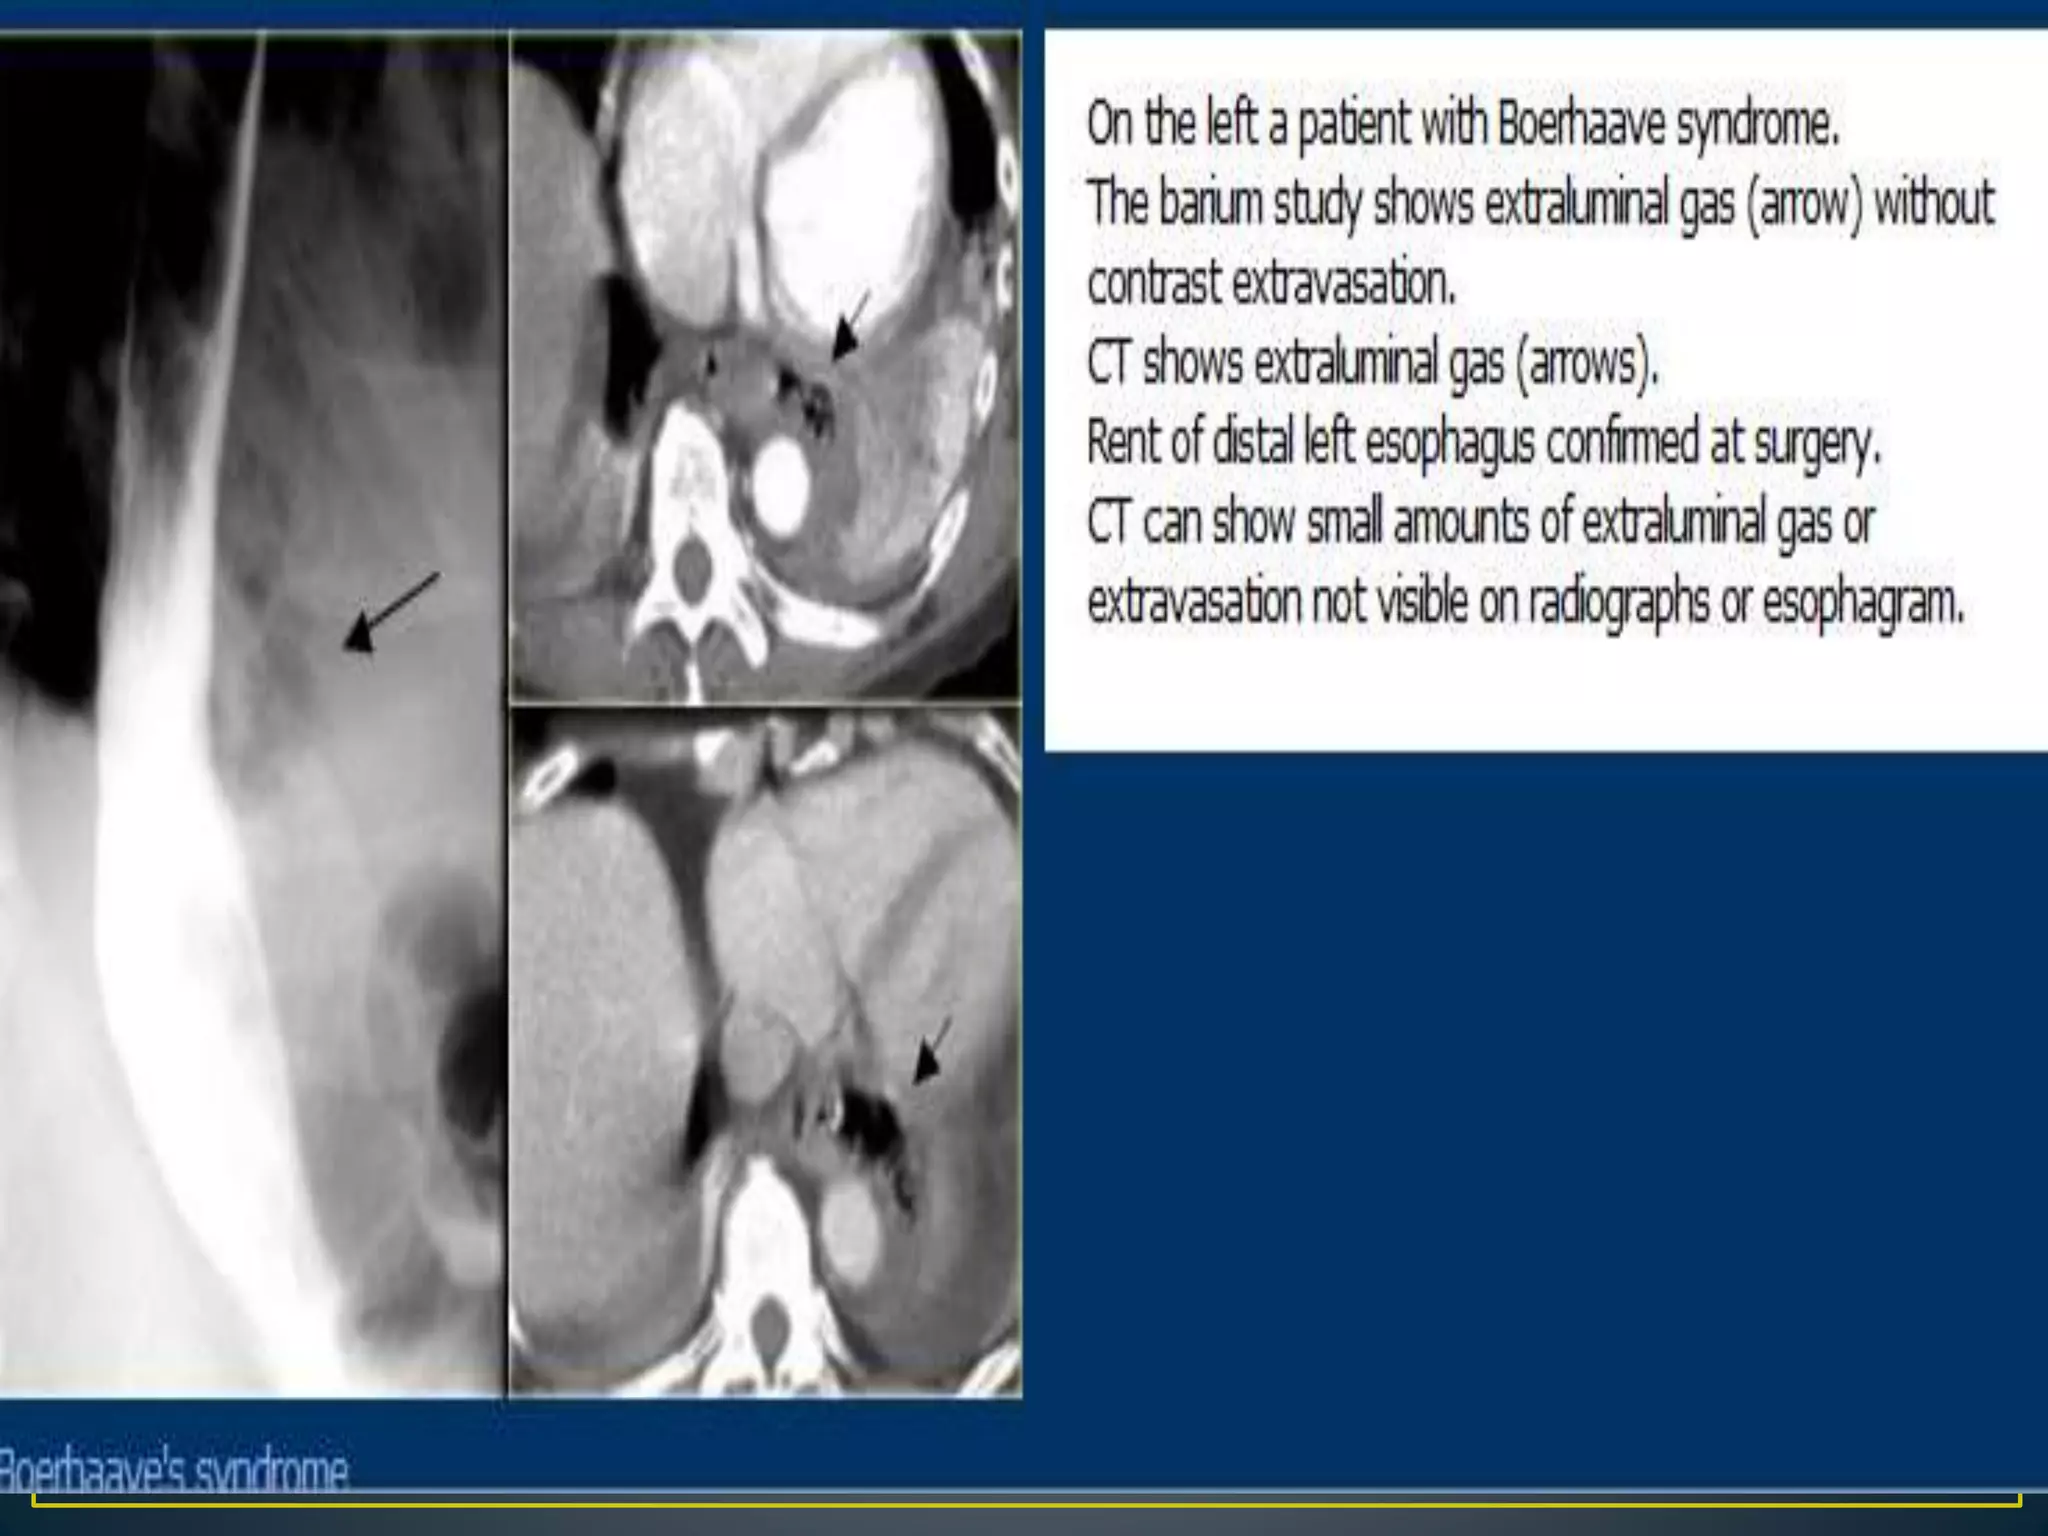

• Boerhaave syndrome is rupture of the esophageal wall.

It is most often caused by excessive vomiting in eating

disorders such as bulimia although it may rarely occur in

extremely forceful coughing or other situations, such as

obstruction by food.

Boerhaave syndrome is a transmural or full-thickness

perforation of the esophagus, distinct from Mallory-Weiss

syndrome, a nontransmural esophageal tear also associated

with vomiting.

These syndromes are distinct from iatrogenic perforation,

which accounts for 85-90% of cases of esophageal rupture,

typically as a complication of an endoscopic procedure,

feeding tube, or unrelated surgery.

• LEFT ANTEROLATERAL WALL IS MOST COMMONLY